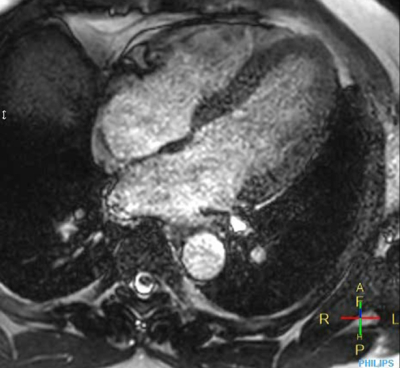

Cine 2D BFFE (4 CAV)

Elition X 3.0T

Metropolitan Police Hospital w Tokio, Japonia